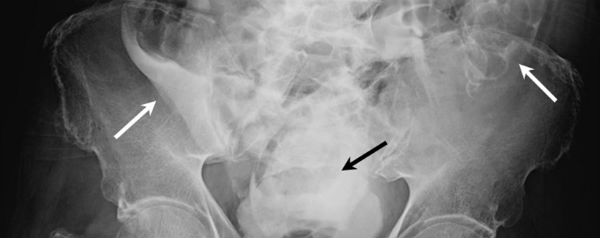

In de praktijk zal de plasreflex echter te sterk worden om hem te onderdrukken. Er zijn wel gevallen bekend waarbij de blaas scheurde, maar daarbij ging het om mensen met kanker of gebeurde het tijdens een bevalling. De urine komt dan in de buikholte terecht (zie de pijltjes op de foto) en geeft ontstekingen, die onbehandeld tot de dood kunnen leiden.